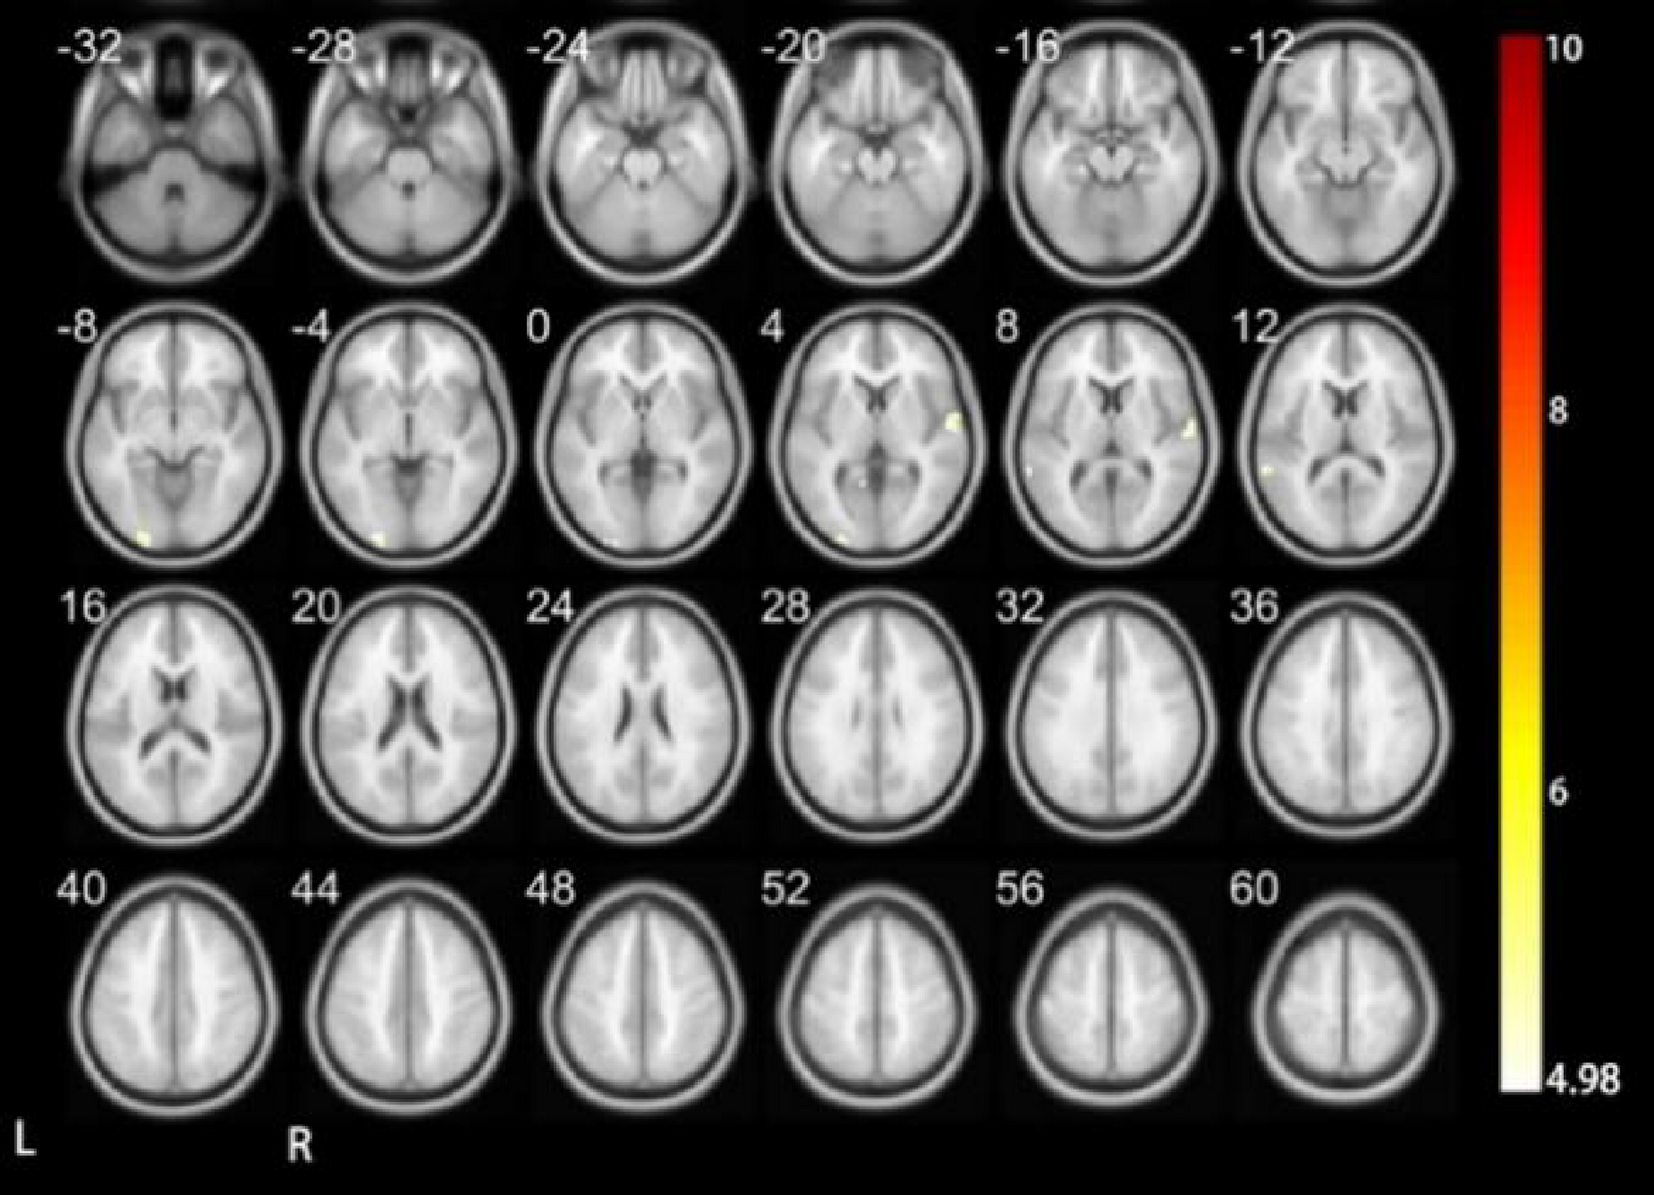

Fig. 8

Results of executing the vocal tones four-time DC.